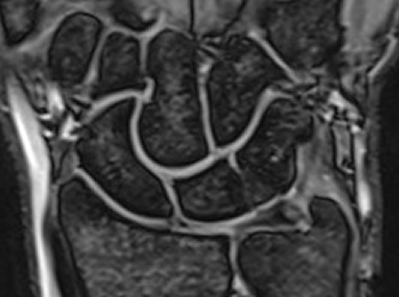

Magnetic Resonance Imaging showed a bone marrow edema adjacent to the fibro-cartilage coalition as well as hyaline cartilage in the distal notch (Figure 3 [Fig. 3], Figure 4 [Fig. 4]).